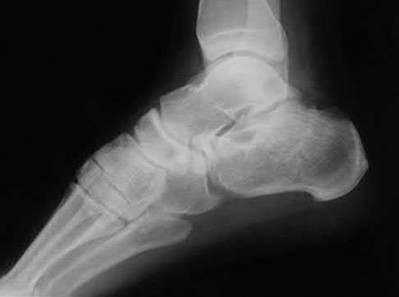

A 34-year-old male sustains the closed injury seen in Figure A as a result of a high-speed motor vehicle collision. What is the most appropriate next step in treatment?

The radiograph shows a comminuted pilon fracture, which is associated with high-energy trauma and significant soft tissue injury. The tested concept here is the importance of avoiding definitive reduction and fixation of this high-energy injury, which has been shown to be associated with an increased risk of wound complications and deep infections (as compared to staged treatment with usage of a spanning external fixator).

Patterson et al. reviewed 23 consecutive patients with comminuted distal tibia fractures. They showed 0% infections or wound-healing problems in their patient population treated with a two-staged protocol. Their protocol involved fibula fixation with an intramedullary implant and application of a medial external fixator to to regain length and restore anatomic alignment. Reevaluation of the limb occurred ten to fourteen days later for definitive fixation.

Sirkin et al. retrospectively reviewed 40 closed and 17 open pilon fractures (AO types 43A-C) that were treated with staged surgical management (avg. time from ext. fix. to formal reconstruction was 14 days (range 4 to 31) They reported 17% post-operative wound complication in the closed group and 11% post-operative wound complication in the open group (Gustilo Type I-III). They suggest the technique was successful in both closed and open pilon fractures.